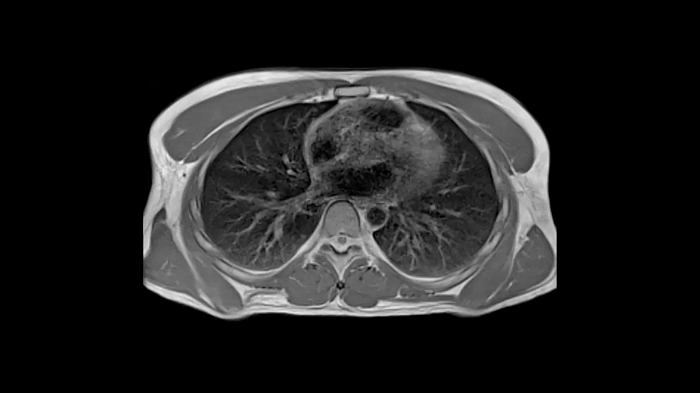

New opportunities in pulmonary imaging with High-V MRI

Pulmonary imaging has been disreputably challenging with traditional MRI as the air-tissue interfaces lead to fast signal decay. These challenges scale with magnetic field strength which makes High-V MRI the perfect opportunity for pulmonary imaging. Consequently, High-V MRI has the ability to extend the reach of pulmonary MRI.

Image Courtesy: University Hospital Erlangen, Germany | Image-ID: 4aaaa0419